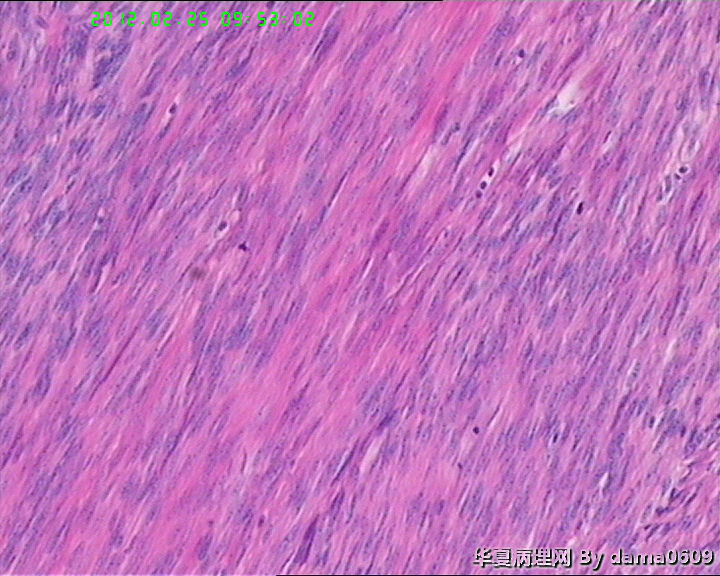

学生问题:1、这样的坏死在子宫平滑肌瘤中常见到,肉眼观界清,镜下坏死灶与周围正常组织陡然分界,无移行带,又不见明显炎细胞浸润,故怀疑是否为凝固性坏死??坏死灶内坏死平滑肌细胞无异形性,但轮廓清晰可辨,是否为“鬼影细胞”?

2、此例坏死灶周围平滑肌组织核分裂像很容易见到,时而一个高倍视野竟有四个,如何解释、诊断?再者学生对平滑肌细胞核分裂像也不肯定,请老师指教,应该不是核固缩。

• 子宫肌瘤坏死,是何性质?!请指教!图2

图2